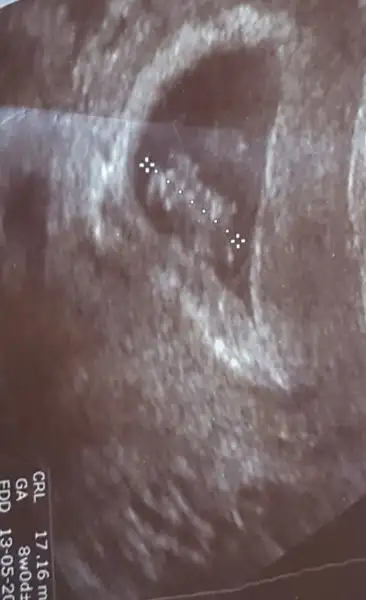

Bence bu bebiş erkekŞurayada dünki ultrason görüntüsünü bırakıyorum.

Henüz küçük canım sanirim pek belli olmuyor gibi ya da ben göremedimBu arada guzel kalbinin atisini da duydum ilk kezcinsiyet tahmini olabilir mi sizce

MaşallahBu arada guzel kalbinin atisini da duydum ilk kezcinsiyet tahmini olabilir mi sizce

Kucuk evet ve de cok bulanik ben gene de sansmi deniyim dedimHenüz küçük canım sanirim pek belli olmuyor gibi ya da ben göremedim

Maşallahama cinsiyet tahmini için birazcık daha beklemen gerekiyor sanırım